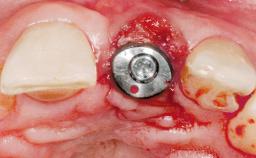

Late Placement of an Implant in a Maxillary Left Central Incisor Site

# of Implants 1

Type of Implants Two-Piece

Bone Augmentation Horizontal|Staged

Augmentation Materials Xenogenous|Membrane

Placement Protocol Early or late implant placement

Bone Volume Deficient horizontally, requiring prior grafting